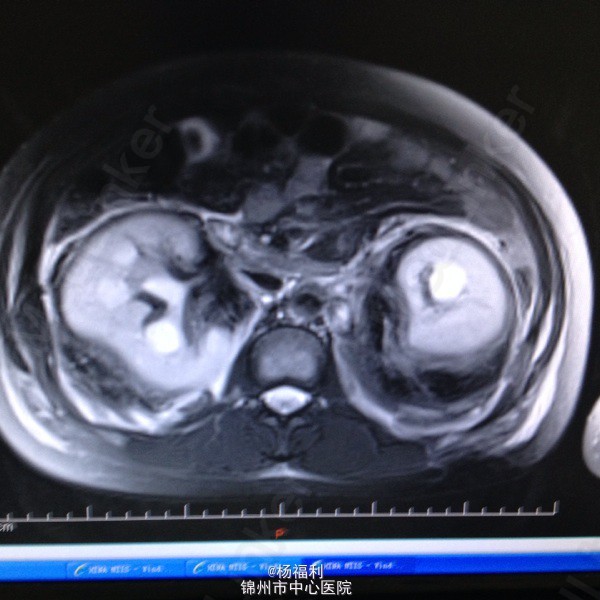

44岁女患。为消化科我会诊患者。 现病史:以上腹痛9小时为主诉入院。无发热及寒战、噁心未呕吐,无腹泻及黑便。 既往史:双眶炎性假瘤2年,口服激素治疗,并补钾。

查体:上腹部压痛,无反跳痛、右侧压痛明显,右肾区叩击痛,左肾区轻叩击痛,双输尿管走形区无压痛。 辅助检查;泌尿系彩超:双肾积水。 血白细胞:9.99*10^9。 肾功能正常。 全腹部ct及MRU检查:见图片。

诊断;真的不知道是啥病。 处理:暂时止痛处理。双肾病变。不知从哪里下手。